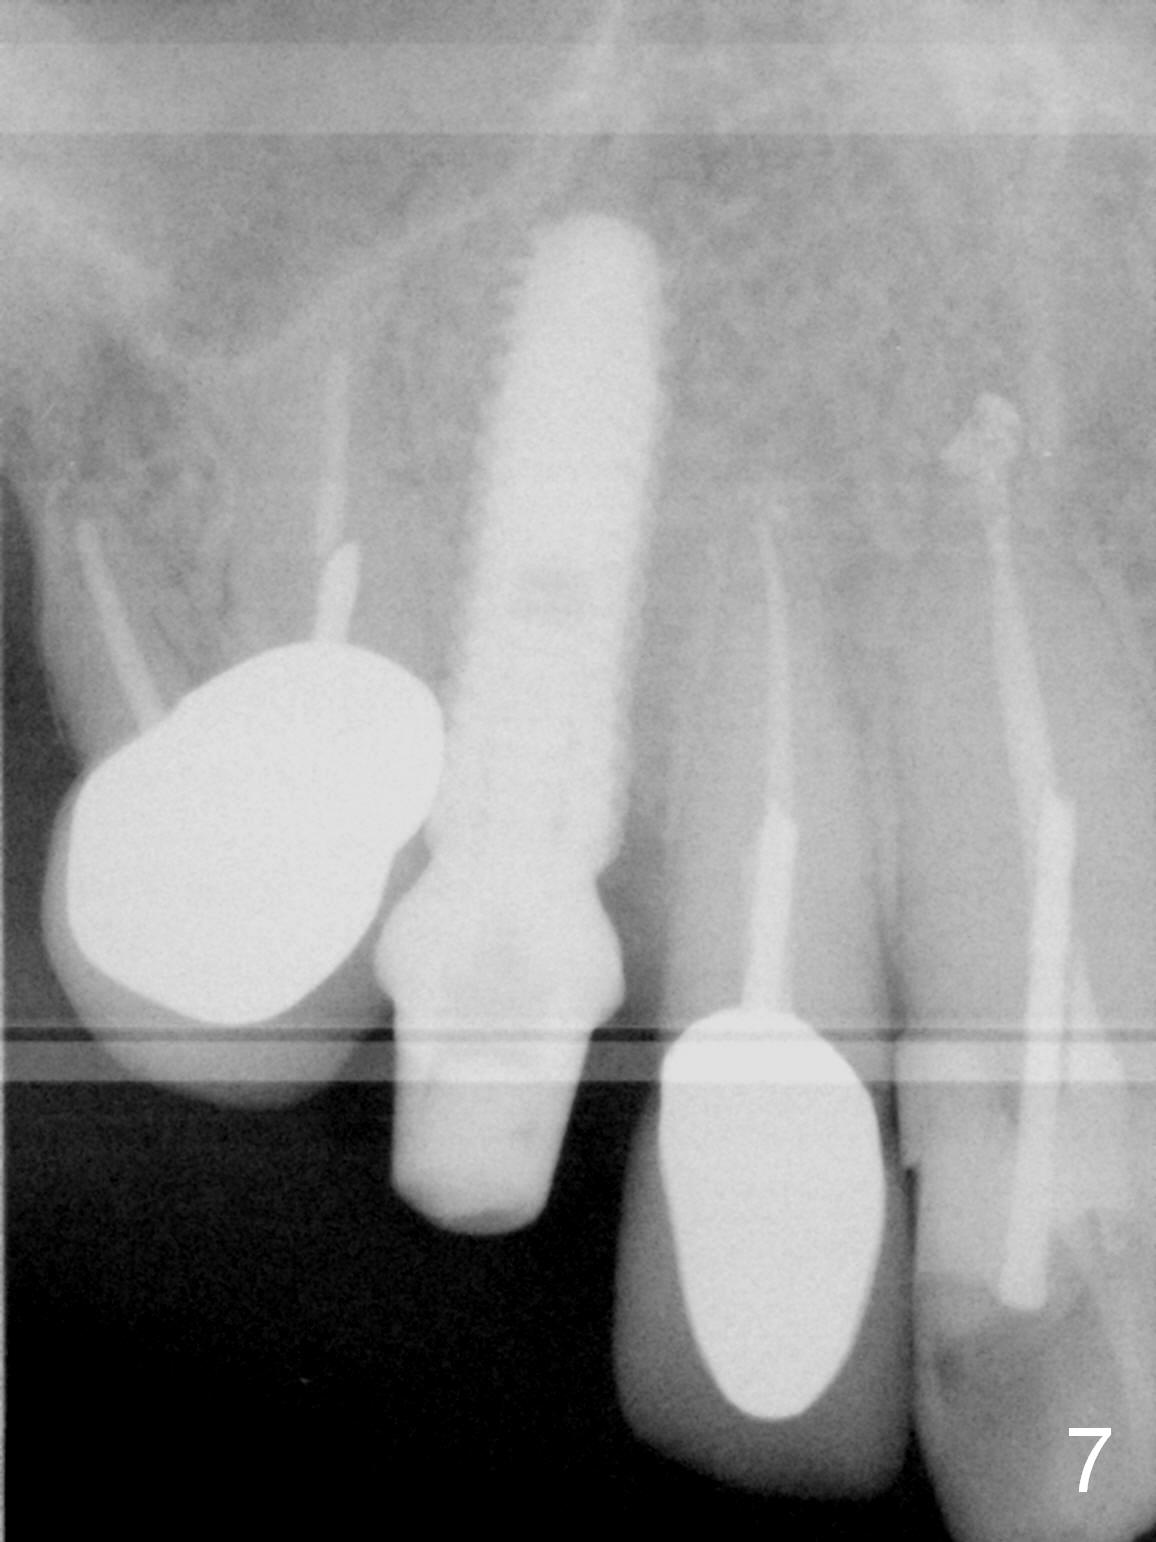

Three months postop, the provisional is dislodged (Fig.7-9). The mesial gingiva is hypertrophic buccally (Fig.8 *) and lingually (Fig.9 *). There appears to biologic width violation (Fig.5). The abutment should be changed to the one with smaller in diameter and longer in cuff (4.5x5(4) mm) with the buccal margin reduction.